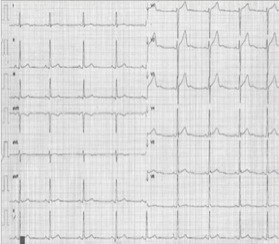

ECG:

- Ritmo sinusal.

- Frecuencia cardiaca de 60 lpm.

- Eje eléctrico normal a +80º.

- Ondas P de morfología normal

- Intervalo P-R de 0.20 s.

- QTc de 0.41s.

-Hipertrofia ventricular izquierda secundaria a sobrecarga de presión sistólica -> Índice de Sokolow-Lyon positivo ( ondas S profundas en derivaciones precordiales derechas (V1, V2) y R altas en las izquierdas (V5, V6).